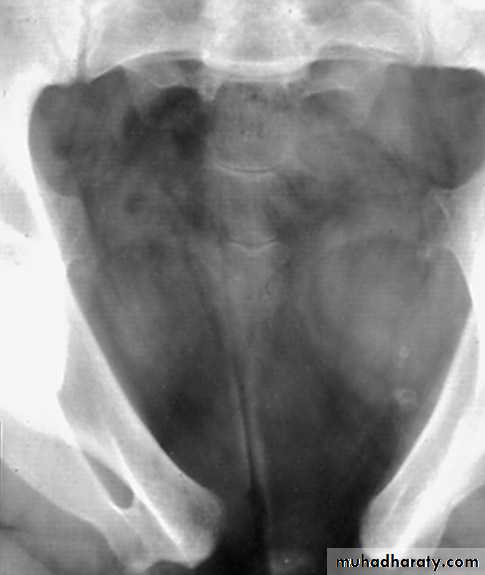

Ectopia vesica (bladder exstrophy).

Exstrophy of the urinary bladder is a complete ventral

defect of the urogenital sinus & the overlying skeletalsystem.

Other congenital anomalies are frequently associated

with it. The lower central abdomen is occupied by the

inner surface of the posterior wall of the bladder,

whose mucosal edges are fused with skin.

Urine spurt onto the abdominal wall from the ureteral

orifices.

The rami of the pubic bone are widely separated.

The pelvic ring thus lack rigidity, the femurs arerotated externally, & the child waddle like duck.

by ureterovesical obstruction may be found on theurography.

These films also reveal separation of the pubic bone.